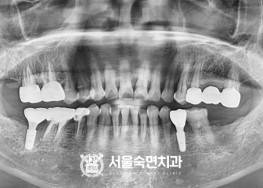

임플란트-치료-전후사진